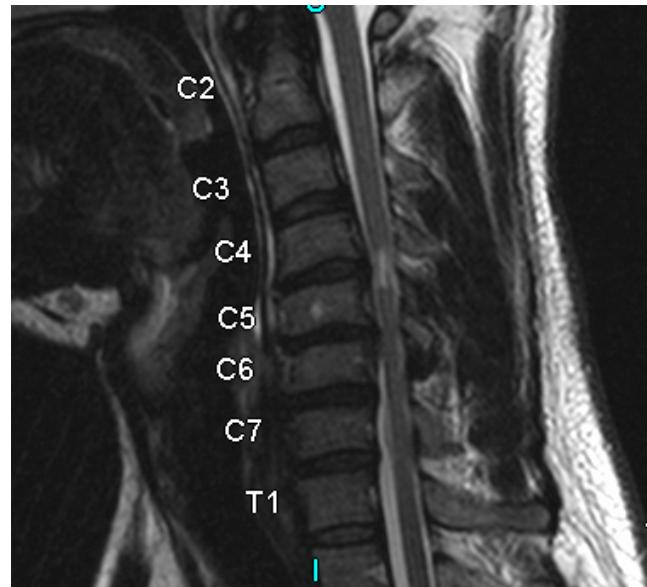

Imaging:

- MRI: Study of choice to evaluate degree of spinal cord and nerve root compression

Imaging Examples:

Surgical Treatment - Anterior Cervical Discectomy and Fusion: